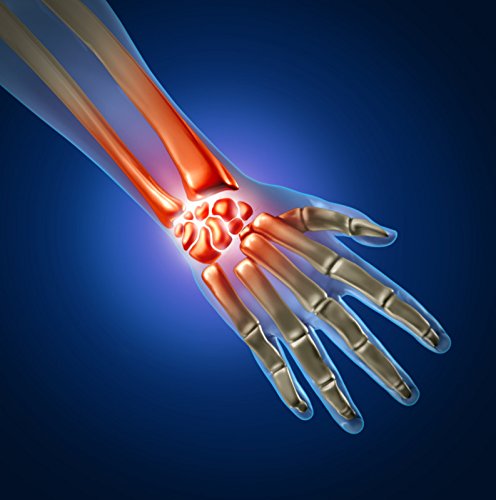

Suffering from carpal tunnel? The Didakay Wrist Hand Palm Support Brace will do the job, day and night, providing support for your wrist at work (think: lots of typing). You can wear it easily with an outfit and it is not "bulky". It flexible yet keeps your wrist stable. Your skin can breathe well in it too. It is also very comfortable at night and light weight. Designed to provide compression and support for stiff, weak or injured joints, this elastic support brace helps provide protection from further injury. 1 brace per package. One size fits most.